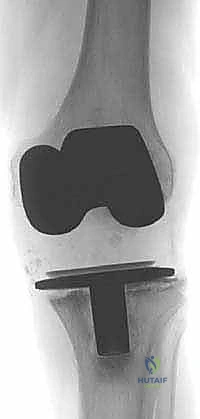

- الأشعة السينية (X-rays): صور متعددة الزوايا لتقييم تخلخل المفصل، هبوط المكونات، وحجم التجاويف العظمية (تحلل العظم).

- الأشعة المقطعية (CT Scan): ضرورية جداً في حالات المراجعة، حيث تعطي صورة ثلاثية الأبعاد دقيقة لحجم وشكل فقدان العظم في قصبة الساق، مما يساعد الجراح في اختيار حجم ونوع الدعامات المطلوبة.